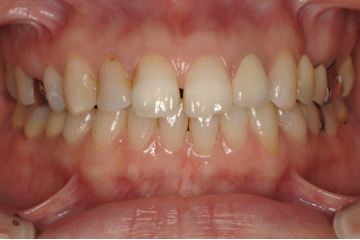

治療例 1

上顎右側1番の被せ物の色が浮いている事を主訴に来院。隣接歯、他の天然歯と比較して違和感のない被せ物を装着しました。